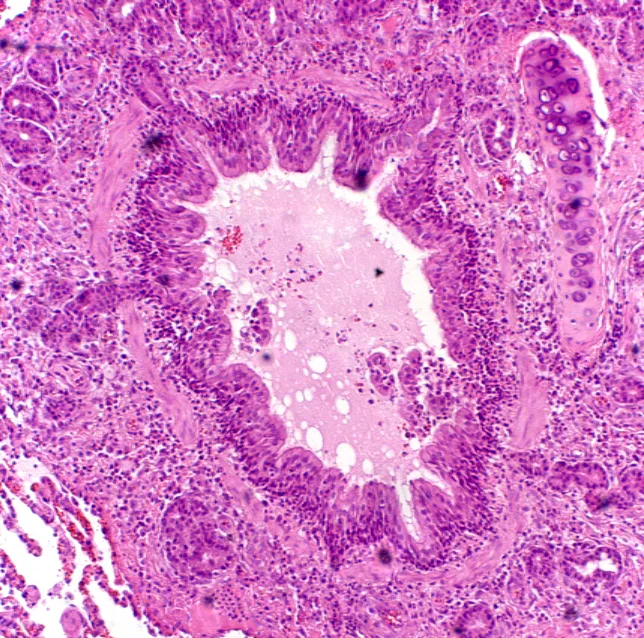

Pathologic changes include airway mucosal changes (epithelial denudation, increased inflammatory cells) and increased goblet cells with intraluminal mucus and inflammatory debris. Substantial subbasement membrane thickening occurs with long-standing disease (ie, airway remodeling) (Figure 2B).

FIGURE 2 A patent airway in a healthy cat (A). An occluded airway from a cat with chronic disease (B). Intraluminal mucus and debris, smooth muscle thickening, numerous inflammatory cells and goblet cells, and subbasement membrane thickening are evident.